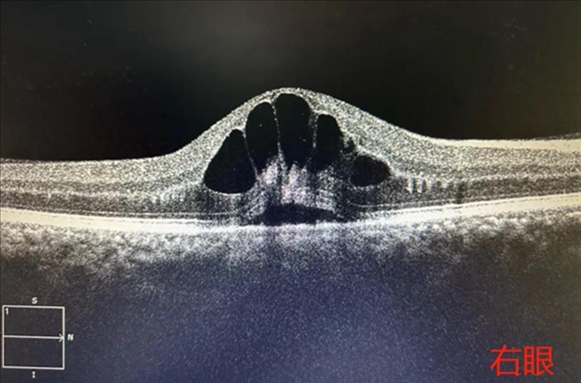

·男子胡吃海喝一周后眼底“長出花瓣”,眼科專家提醒:假期應(yīng)健康飲食。